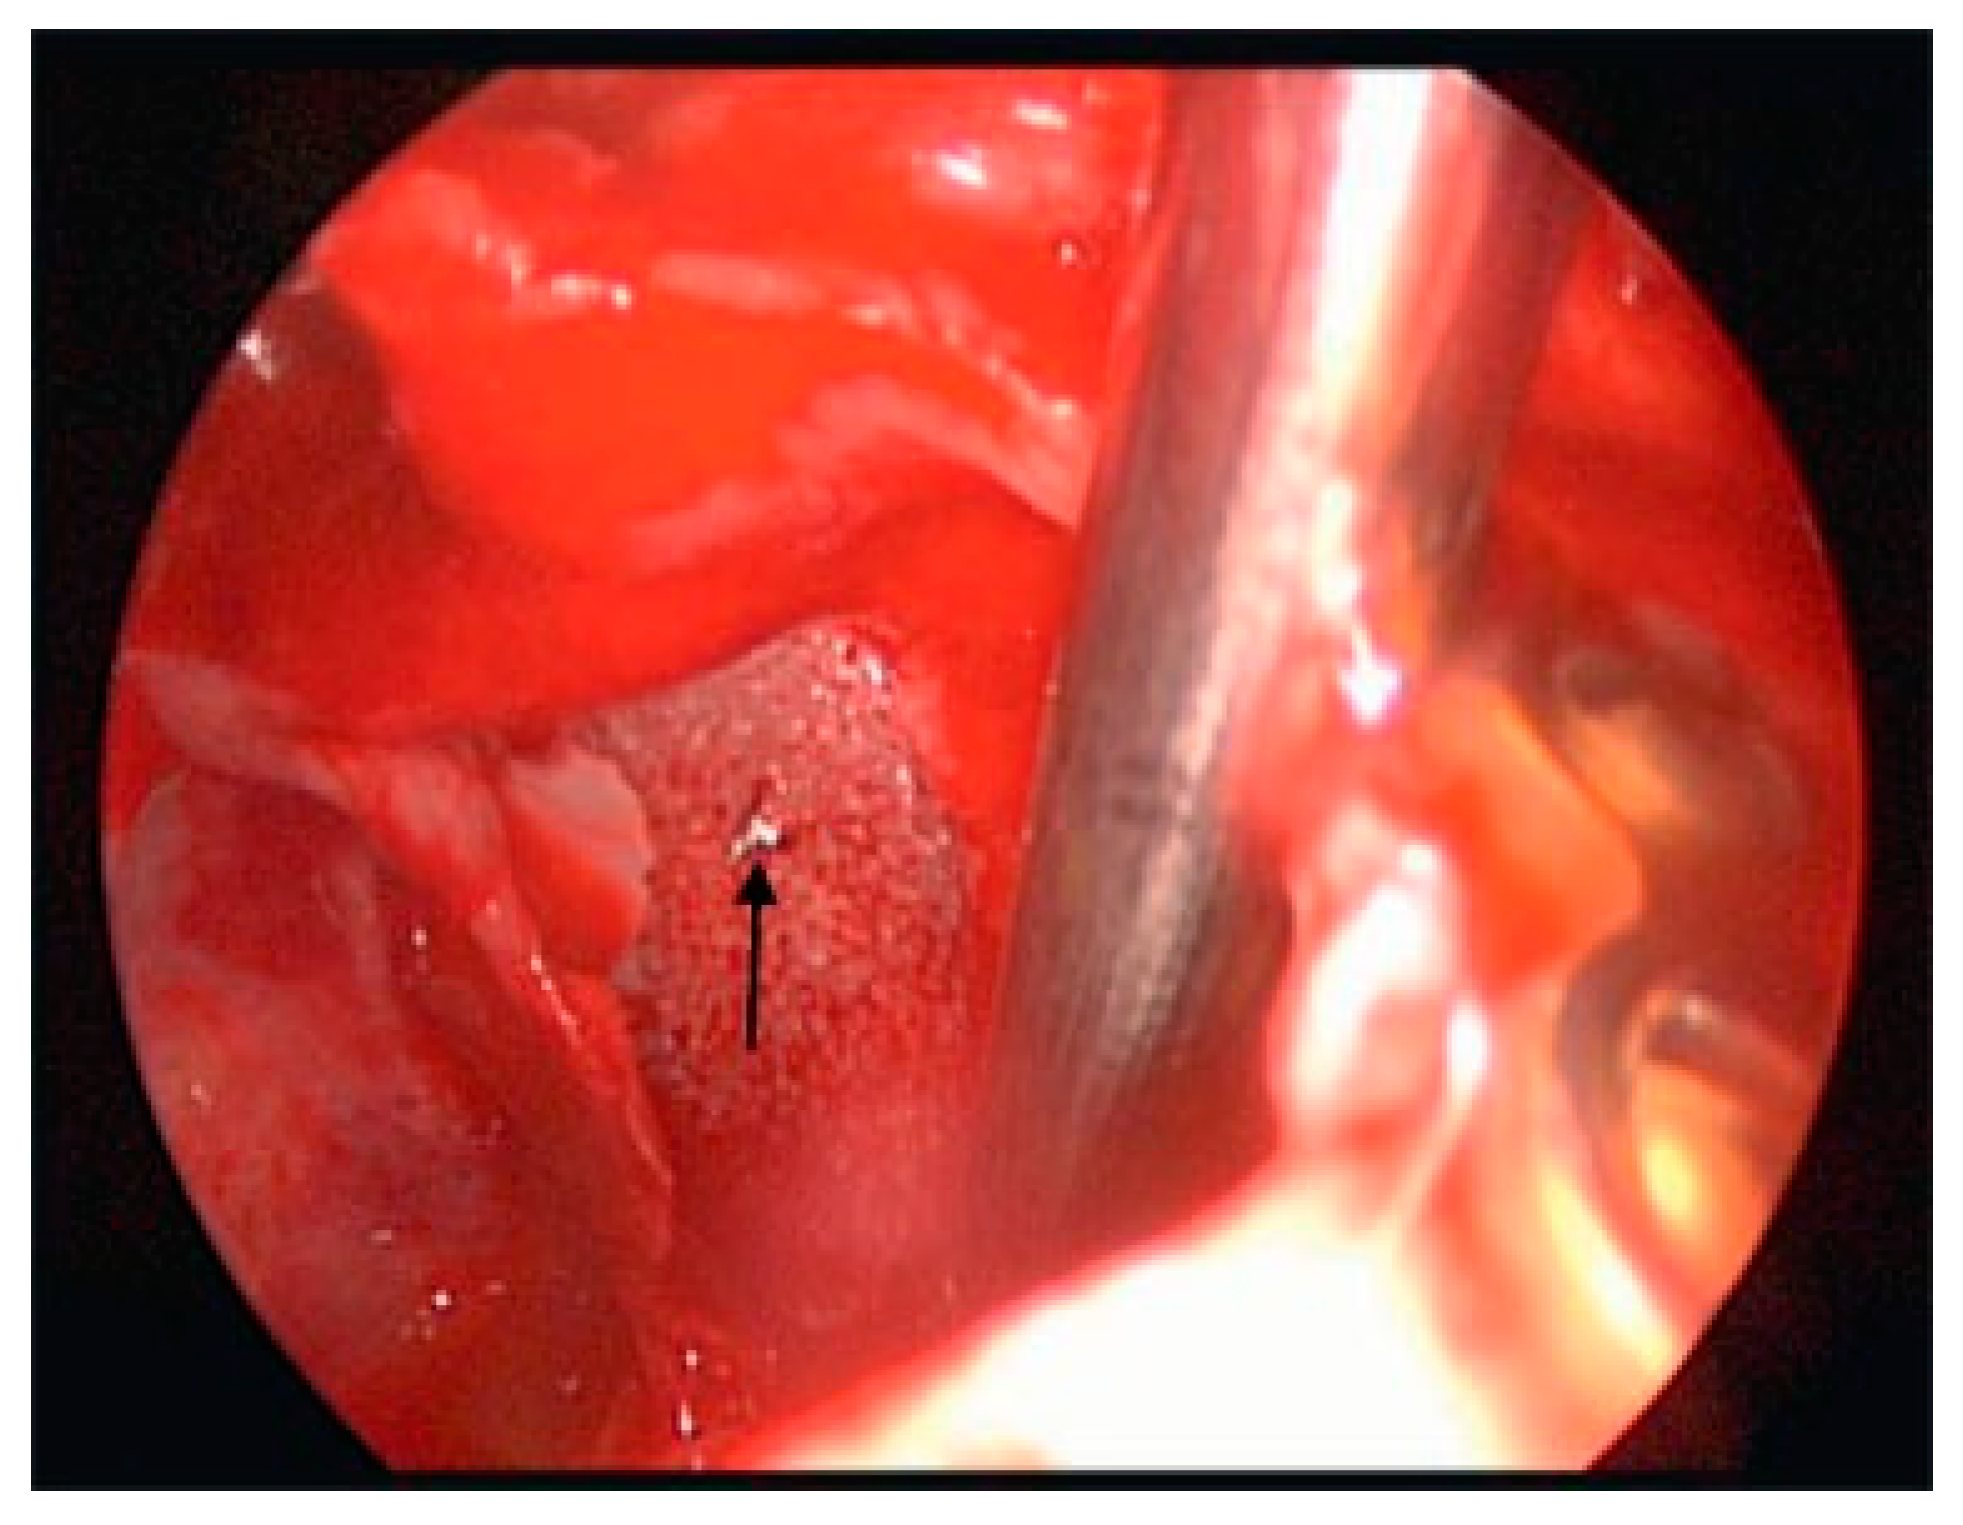

The techniques for endoscopic surgery are the same as for any open procedure, and the instrumentation for endoscopic techniques are frequently similar to open instruments. The main additions are the endoscopes, tower, camera and video monitors. The scopes today are typically Hopkins rods and come in different sizes (2.7 to 4 mm for head and neck purposes) and different angu- lations (0, 30, 45, and 70 degrees). The diameter of the glass rode can have a profound affect on the amount of light and visualization provided. The angle can also affect visualization. The camera is an industrial quality, 3-chip CCD (charge-coupled device), which is the type used for recording movie-quality videos. It is attached directly to the Hopkins rod and transmits the video signal to a tower. The tower has the printer, video equipment, light source, and monitor necessary to show the image to the surgeon. Figure 1, Figure 2 and Figure 3 show the typical instrumentation needed for any endoscopic case. For endoscopic orbital cases, the patient is into-bated and the head of the bed turned so the surgeon is on the patient’s right side. The video monitors are placed at the patient’s head for transantral orbital surgery and at the feet for endoscopic frontal sinus surgery. The gingivobuccal sulcus is then injected with local anes- thetic containing 1:100,000 epinephrine. This requires ~10 min to be maximally effective. Once the vaso-constriction is complete, a sulcus incision is made. The maxilla is stripped of periostium. Before beginning, we bend a plate for the end of the procedure. Then a 2-cm wide by 1-cm long Caldwell-Luc antrostomy is per- formed. We usually leave the bone as an osteoplastic flap for closure. Once the antrostomy is made, the intrasinus contents are cleared and decongested. After this is achieved, the nasal cavity is inspected. The roof of the sinus can now be visualized. If the patient has a trapdoor type fracture, the mucosal flaps can be raised and the bony fracture carefully opened so that the entrapped content can be replaced into the orbit. If the patient has a full-size defect, the opening should be inspected to ensure that none of the fragments are present within the orbital fat or in the inferior rectus muscle. Also of importance is the infraorbital nerve. It is extraorbital until the fissure is identified, and then it becomes intra- orbital. Care should be taken not to entrap this structure by the plating system. Figure 4, Figure 5 and Figure 6 show an antrum and the fracture in the floor.

Figure 4. Left orbit mucosal tear with inferiorly displaced medial segment (arrow).